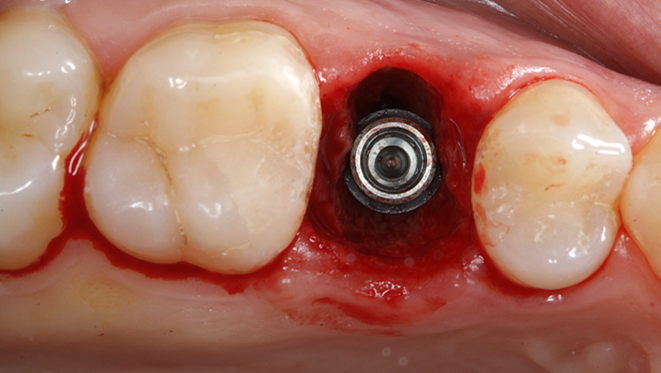

Clinical case: Extraction, immediate implant placement, & provisionalization

- Courtesy of Dr. Iulian Filipov, Romania -

AnyRidge, R2GATE, guided surgery, immediate placement, immediate provisionalization, initial stability, Dr. Iulian Filipov, #25, maxillary posterior, immediate loading, Mega ISQ

Products:

AnyRidge implant system, R2GATE, MEGA ISQ, Digital prosthesis